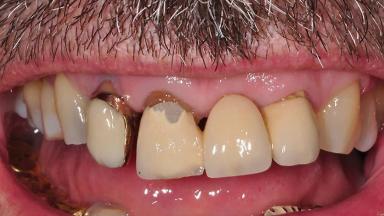

Surgical treatment of a 67-year-old male patient exhibiting an extended edentulous space in the anterior maxilla after the removal of three hopeless incisor teeth.

The case concludes with the presentation of the final prosthesis and the esthetic outcome, demonstrating stable soft tissue conditions and stable bone crest levels at the 3-year follow-up.